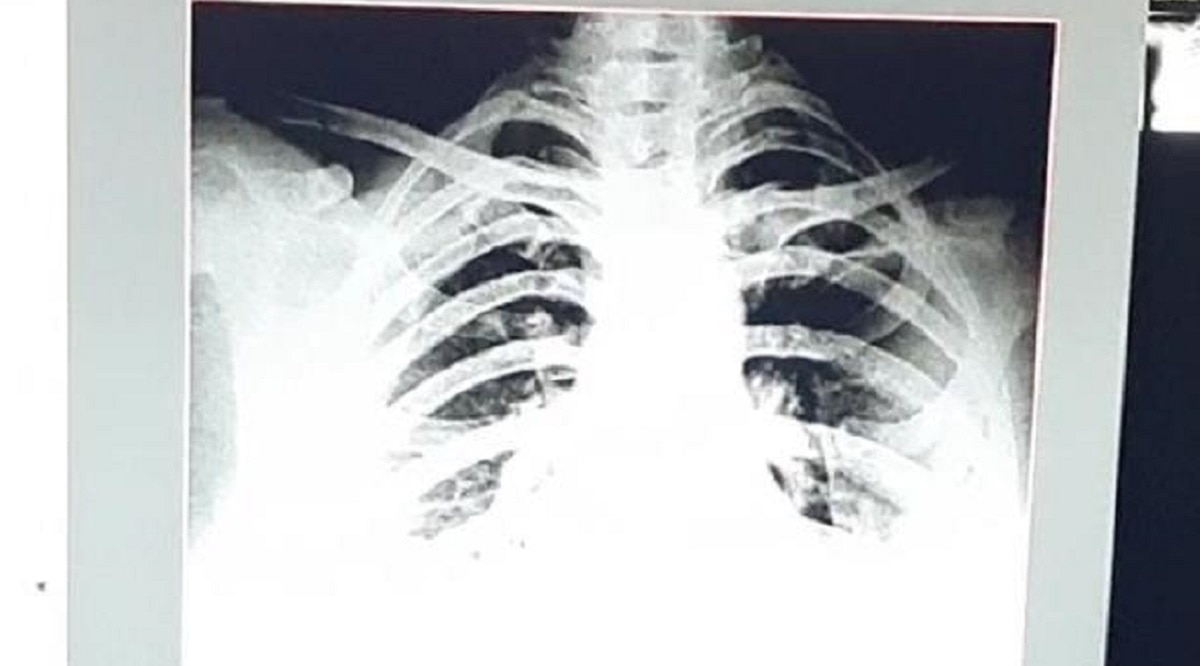

दरअसल, यह मामला कोटा का है, यहां एक 32 साल की महिला का 9 तारीख को एक्स-रे कराया तो वह ठीक थी, 12 तारीख तक भी वह महिला ठीक थी. बीपी, ऑक्सीजन लेवल, एक्स रे सब ठीक था. इसके बाद 12 तारीख की रात को घबराहट महसूस हुई.